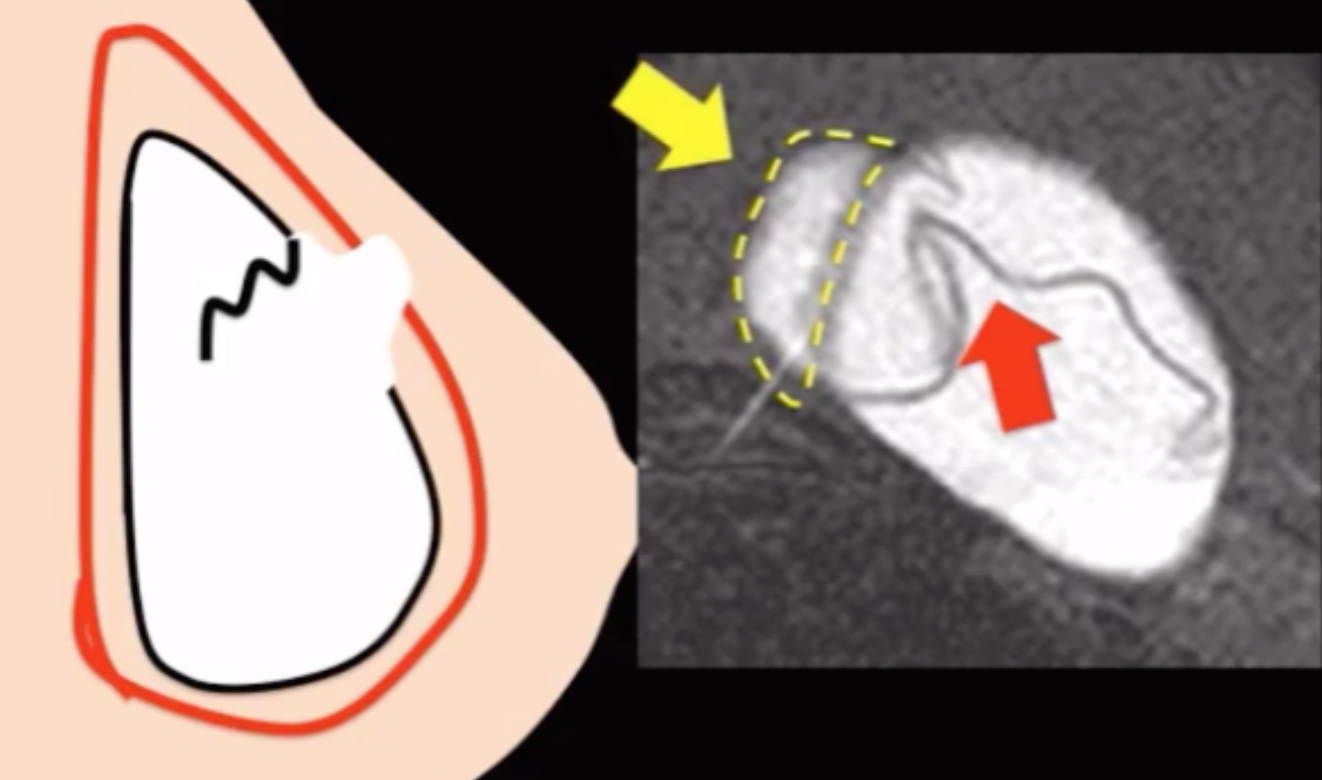

• Intracapsular rupture (80%) - Image 1

• Rupture of the container of the silicone implant but not the actual capsule (soft tissue capsule) itself

• Called linguine appearance

• Squiggle line will not have attachment to wall (radial fold will!)